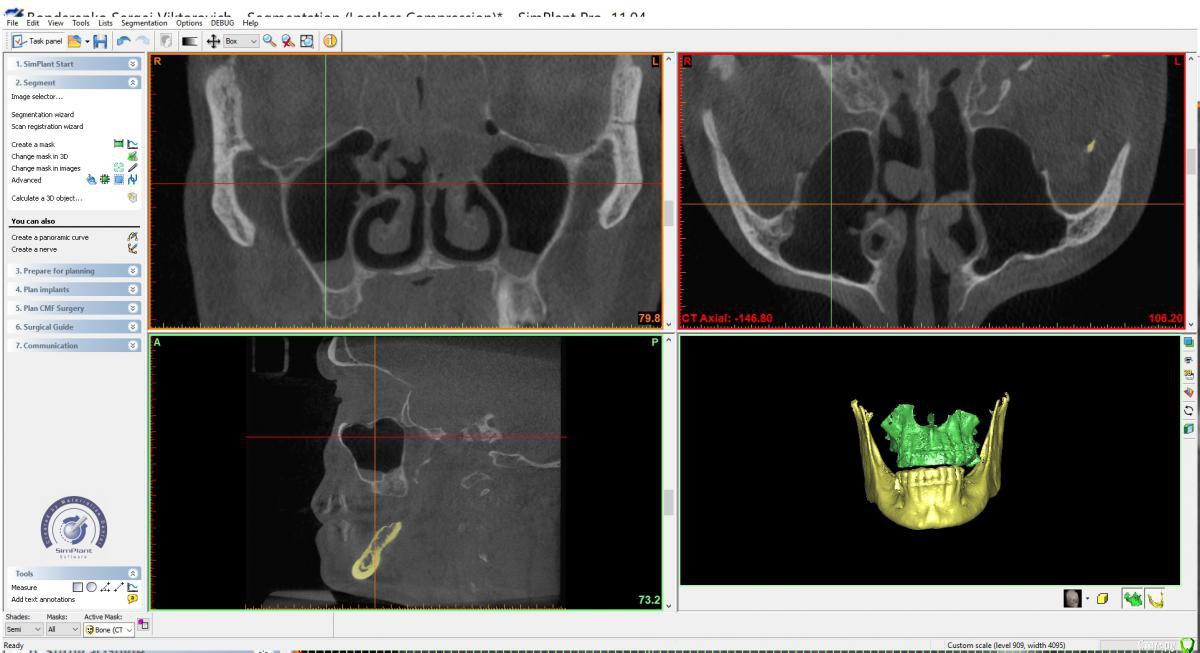

x4ex Опубликовано 7 ноября, 2018 Поделиться Опубликовано 7 ноября, 2018 Добрый день, коллеги! Планируется синус-лифт справа, по словам пациент ЛОР сказал, что противопоказаний не видит. Якобы есть полипы, которые он может убрать эндоскопически, но смысла в этом не видит, потому как со временем они вырастут снова. Но мне картина на КТ похожа не на полипы, а на жидкость с пузырьками воздуха. Кто что думает, стали бы синусить? Ссылка на комментарий

x4ex Опубликовано 7 ноября, 2018 Автор Поделиться Опубликовано 7 ноября, 2018 (изменено) Синусить не стоит, КТ соустья бы ещёпохоже, что соустье закрыто Изменено 7 ноября, 2018 пользователем x4ex Ссылка на комментарий

x4ex Опубликовано 7 ноября, 2018 Автор Поделиться Опубликовано 7 ноября, 2018 я бы 3 коротких поставил. слизистая не гипертрофирована по стенкам-соустье должно открытым быть!ОРВИ во время снимка не было? не вижу соустья. ОРВИ говорит не было, на прошлом снимке год назад ещё хуже. Ссылка на комментарий

x4ex Опубликовано 11 ноября, 2018 Автор Поделиться Опубликовано 11 ноября, 2018 Судя по срезу, там гайморит вторичен. Пусть ЛОР посмотрит этмоидальные..ЛОР в заключении написал "полипозный этмоидит" Ссылка на комментарий

___49___ Опубликовано 12 ноября, 2018 Поделиться Опубликовано 12 ноября, 2018 (изменено) У пациента , фронтит, гайморит двусторонний и этмоидит в стадии ремиссии (сопли) скорее всего , проблемы чисто ЛОРа . Лучше решать вопрос без задействования синуса ИМХО. Изменено 12 ноября, 2018 пользователем ___49___ Ссылка на комментарий